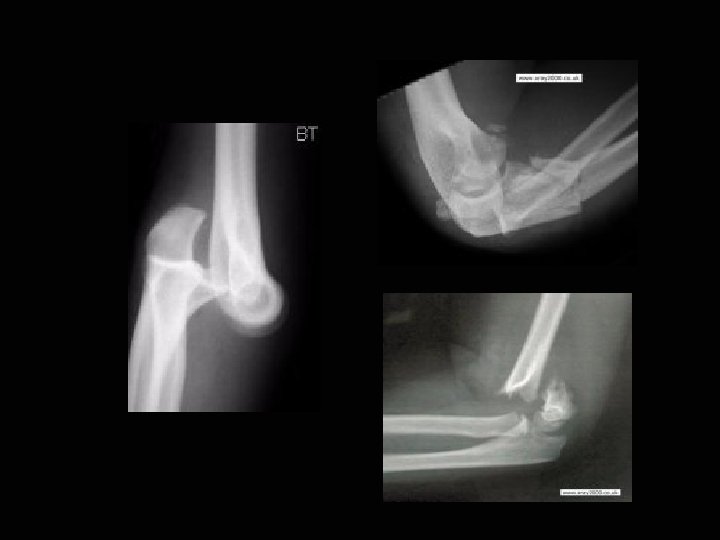

Съдово-нервен слой 1 a. brachialis 2 n. medianus Мускулен слой 1 m. supinator 2 m. brachialis 3 tendo m. biceps brachii Костен слой 1 humerus 2 radius 3 ulna